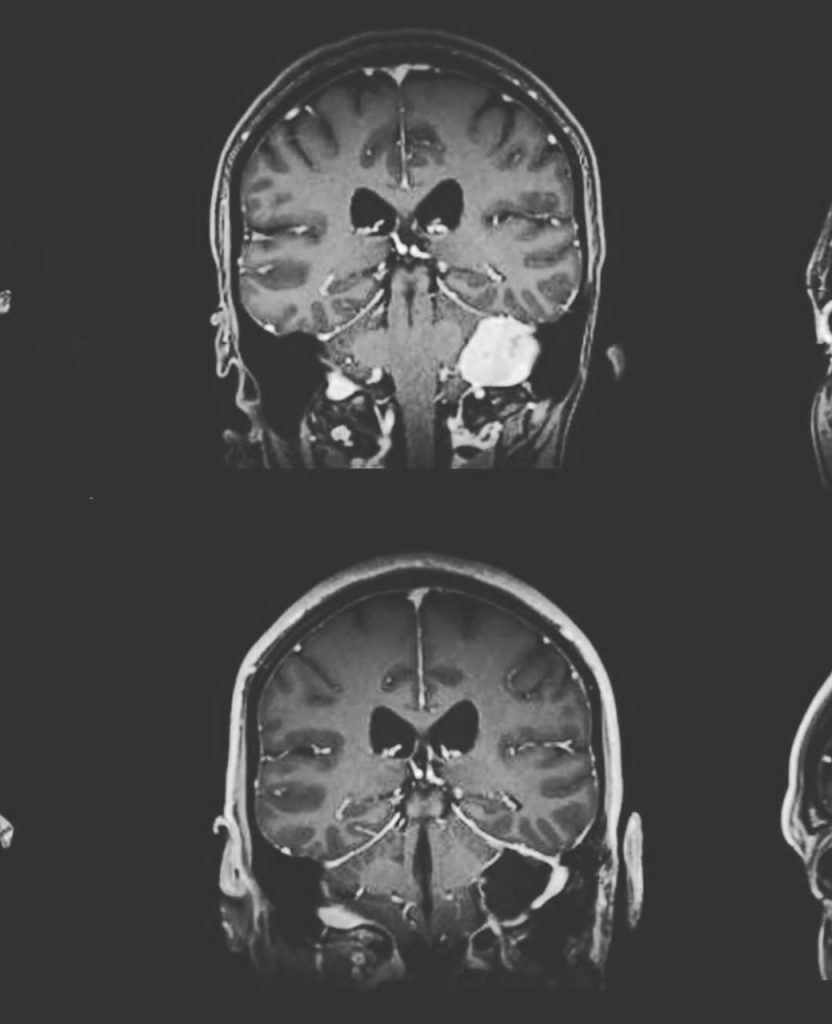

Así lo informó la animadora en sus redes socialles, sonde además indicó que esta operación se produjo luego de que hace meses le descubrieran un tumor, que fue hallado tras una resonancia magnética, como parte de su chequeo anual.

Resaltó que a pesar de que el quiste no resultó peligroso, decidió su extirpación para evitar complicaciones de salud en el futuro.